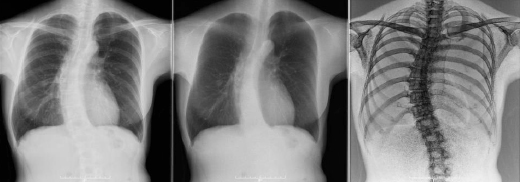

また,「Discovery XR656 Plus」では,搭載されたアドバンストアプリケーションによる詳細な画像撮影が可能となり,機器操作を行う放射線技師の作業効率を高め,診断フローの効率化・適正化に寄与する。例えば,「通常の単純胸部画像だけでは判断のつきにくい陰影も,DESを用いることで,『あるなし』の診断をとても簡便に切り分けることができ,見落としを防ぐ大変価値のある画像を得ることが可能」との評価を得ている*3。

*2:デュアル・エナジー・サブトラクション(DES):骨と軟部組織のX線吸収差を利用し,収集画像に最適な係数を掛けて差分(サブトラクション)することで,単純X線写真に加えて軟部組織(骨除去)画像と骨組織画像を生成する手法

同社一般X線撮影装置XR656 Plus のアドバンスアプリケーションの活用(画像サンプル)